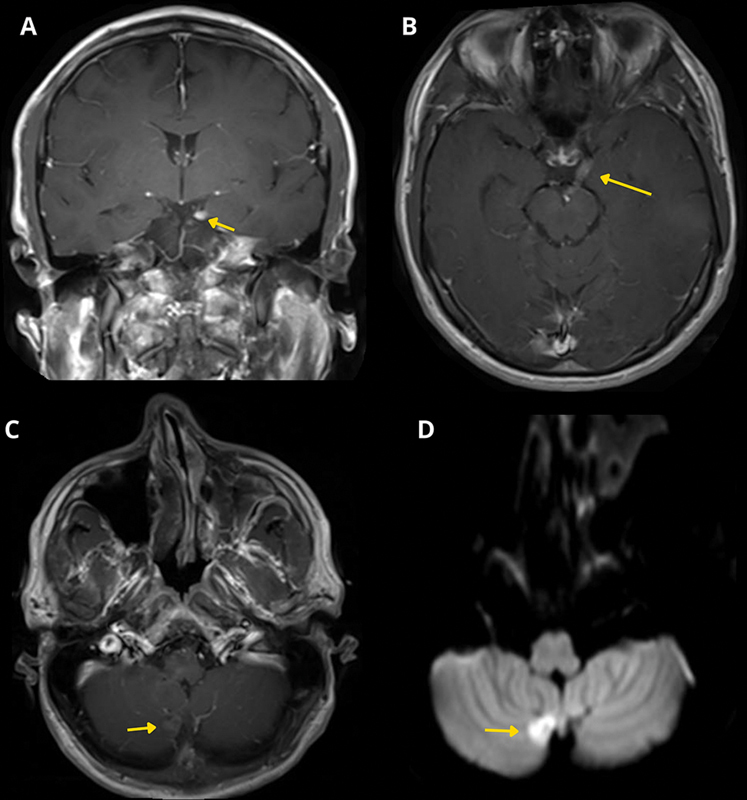

Isolated complete oculomotor nerve palsy as a presentation of adult medulloblastoma.

成人成神经管细胞瘤表现为孤立的完全动眼神经麻痹。